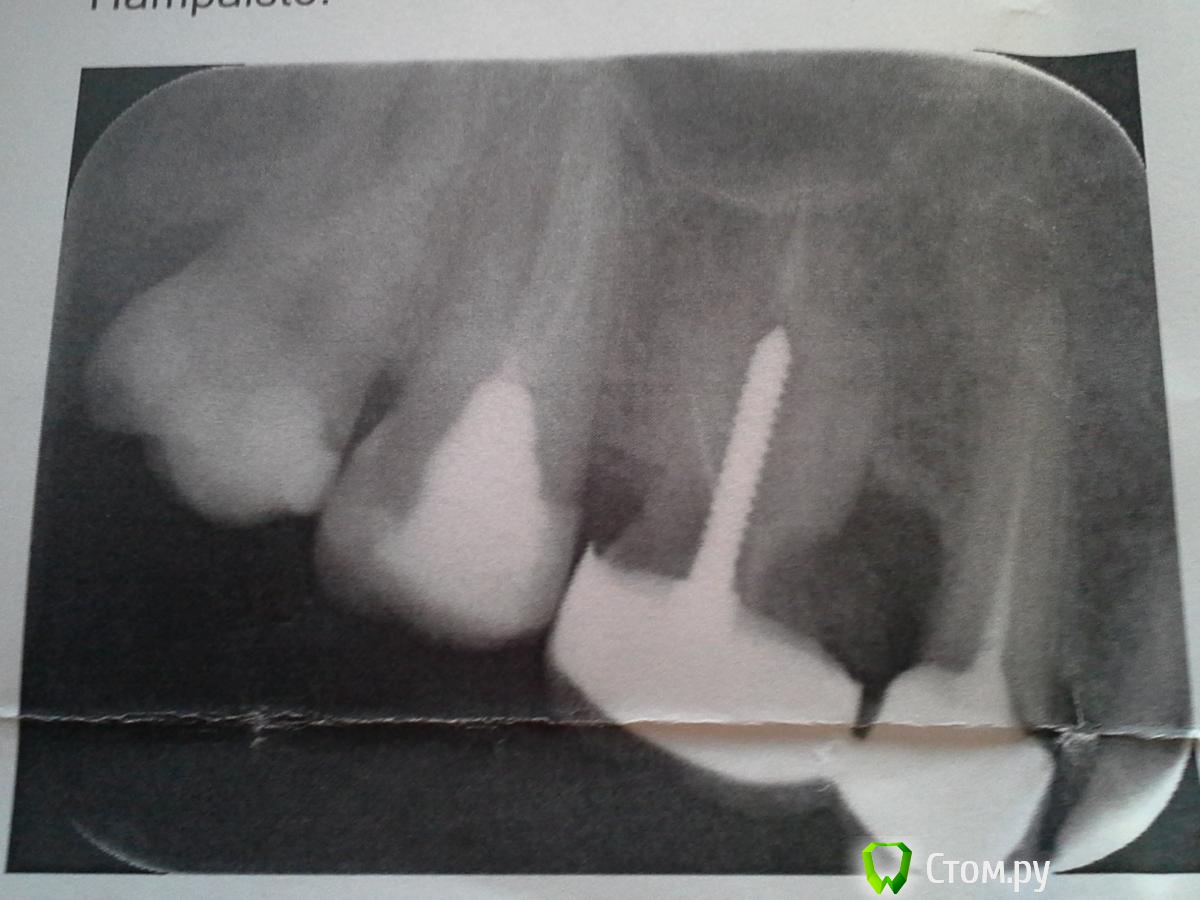

Lerochka Опубликовано 12 июля, 2014 Поделиться Опубликовано 12 июля, 2014 Доброго времени суток!Нужен совет!! В приложенном файле фото давности в 1 месяц.3.5 недели назад сняли двойную коронку (коронка стояла 3 года) и удалили 6-ку (мучаюсь с ней уже 8 лет), положили лекарство в 5-ку, через 1.5 недели снова поменяли, сейчас хожу с лекарством в 5-ке. В 5-ке начал образовываться свищ, который через 3 недели ушел после лекарства. Но нажимать на десну в 6-ке и 5-ке больно.В данной ситуации врач советует ставить мост, обтачив 7-ку, НО подождать при этом пока 5-ка успокоится и не будет больно нажимать на десну. Боль уходит, стало намного легче после лекарства. Сейчас хожу без коронки.ПОСОВЕТУЙТЕ: стоит ли обтачить 7-ку или все же поставить имплант на 6-ку и не делать моста. Оцените состаяние 7=ки. Надо сказать что у меня все задние зубы в широких пломбах. Заранее спасибо! Ссылка на комментарий